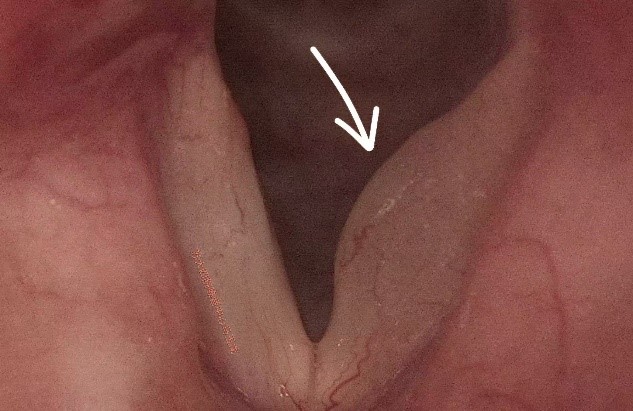

考虑到传统剥脱术式,形成瘢痕的风险较大,术后声音嘶哑风险高,马玉龙副主任医师决定采用“显微镜下声带黏膜缝合技术”为刘女士进行嗓音手术,精准切除水肿组织,最大限度恢复声带振动功能。术后,我院耳鼻咽喉科医疗团队指导刘女士积极恢复,结合禁声管理、呼吸训练,降低粘连风险。1月后,刘女士及家人,专程从上海回苏州复查,声带黏膜恢复良好,嗓音恢复洪亮。